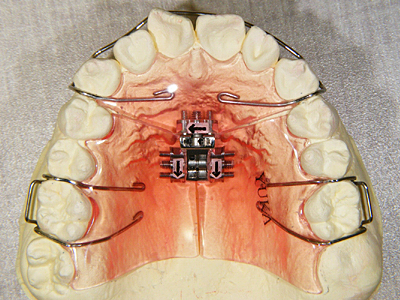

6. 上顎歯列拡大装置

セファロ計測や診断用模型等により、上顎は現段階での劣成長を認めるため、時期が遅いとは思いましたが上顎歯列の拡大目的で(少しでも上下歯列関係は好転したかった)、術前処置として装置にて行いました。